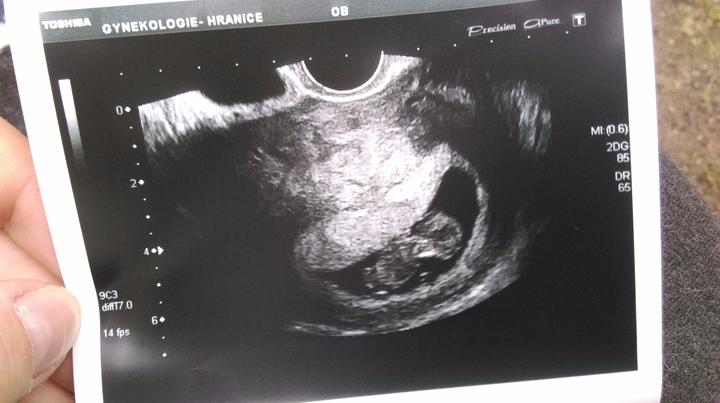

I když bylo moje děťátko rozhodnuté, že se narodí „prdelí napřed“ splnilo mi moje druhé přání a na svět se začalo připravovat v noci v 38+5 (nebo tak nějak - podle mého výpočtu i ultrazvuku jsem byla 39+3). Bylo to dva dny po mojí první prohlídce v Rakovníku, kde mi službu konající doktor doporučil císaře, ale chápal i moje rozhodnutí. Odhadovaná váha byla 3050 g.